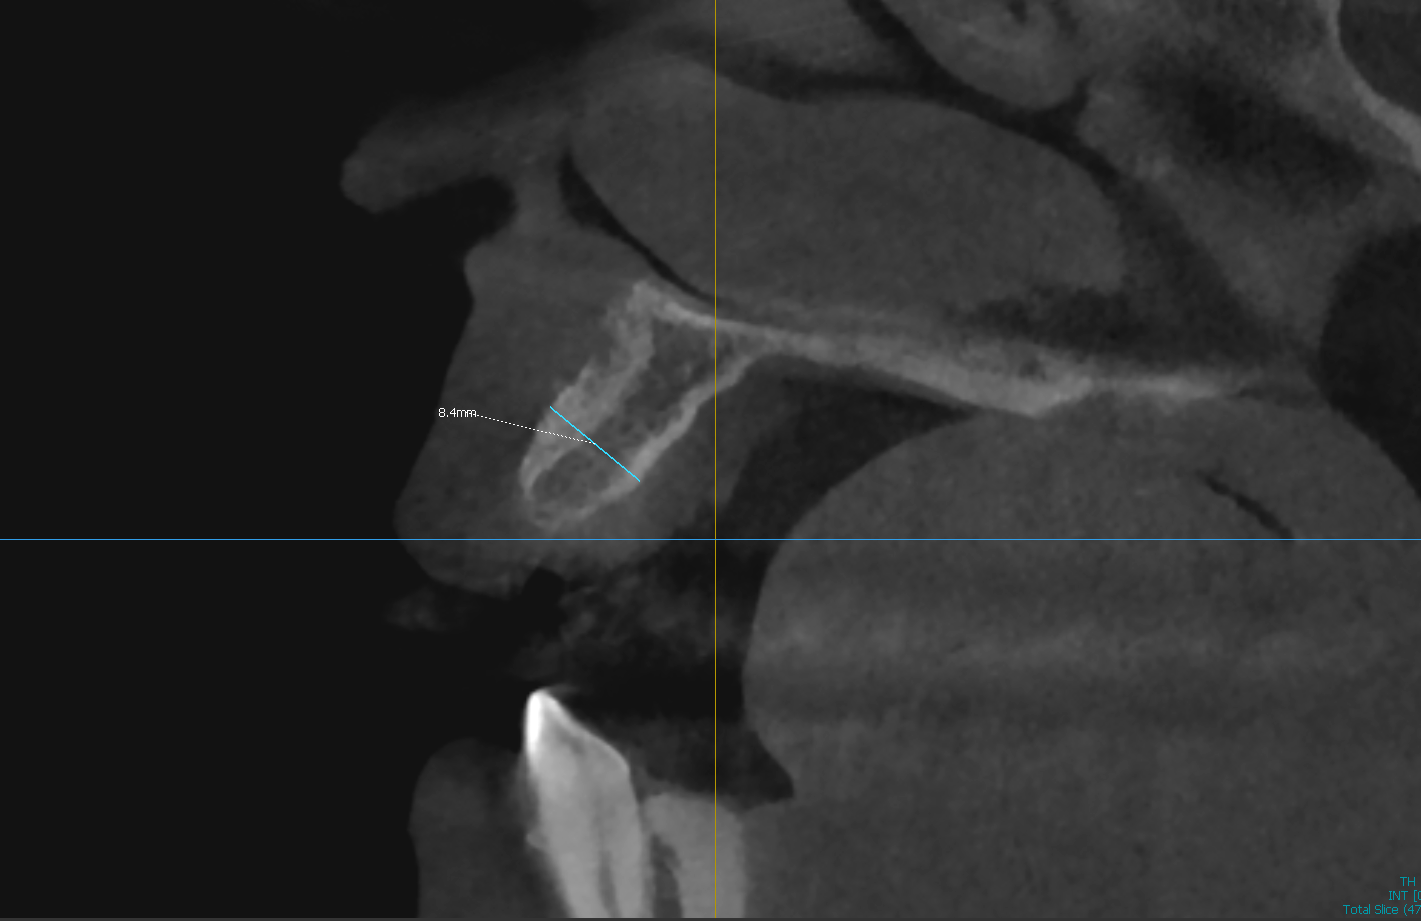

Challenge: Knife-edge ridge in the anterior maxilla presenting with only 4.5mm of width. Insufficient bone volume for implant placement without thread exposure.

Solution: Guided Bone Regeneration (GBR) utilizing particulate graft, resorbable membrane, and fixation tacks to horizontally widen the ridge.

Outcome: Ridge width increased to 8.4mm. Site successfully prepared for ideal, prosthetically-driven implant placement.